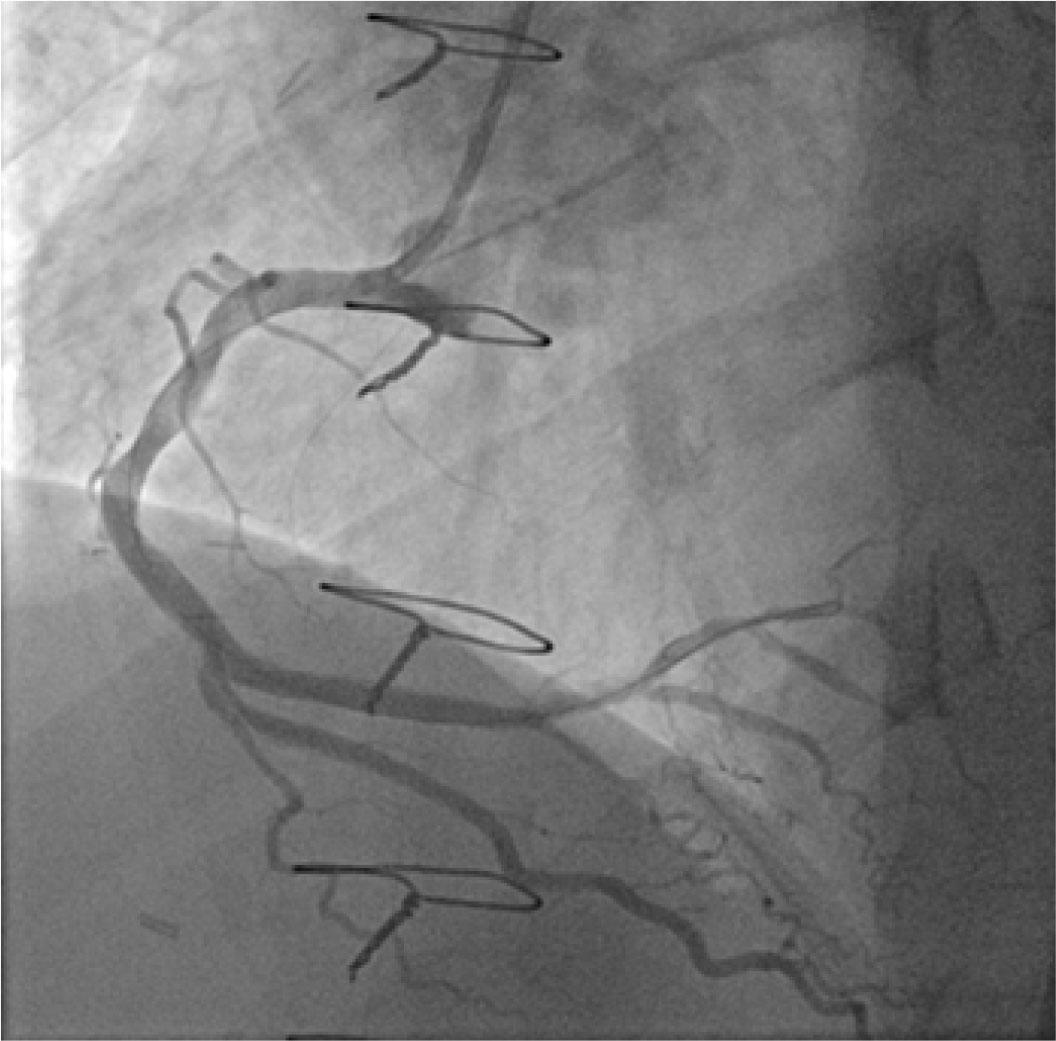

Because the guidewire appeared to be in the false lumen, it was withdrawn and replaced with a 0.014” CHOICE PT Floppy guidewire (Boston Scientific), which was successfully used to cross the lesion. The proximal dissection flap was sealed using a Resolute Integrity drug eluting stent (DES) deployed into the RCA ostium at 16 atm. Afterwards, a buddy wire was used to aid in the delivery of two short Prokinetic Energy 3.5/15 mm (BIOTRONIK) and 3.5/13 mm (BIOTRONIK) bare metal stents (BMS) placed in the distal segment at 14 and 16 atm, respectively. Lastly, a 4.0/38 mm Resolute Integrity stent (Medtronic) was used to cover the culprit lesion and seal off the dissection in the mid-proximal part of the RCA (Figure 3), with a good final angiographic result and restoration of Thrombolysis in Myocardial Infarction (TIMI) grade 3 flow (Figure 4). Final angiography and aortography with pigtail catheter showed complete sealing of the dissection flap. Also, a CT scan conducted two days later showed patent RCA stents with no evidence of dissection (Figure 5). The patient remained asymptomatic on guideline-recommended medication after myocardial infarction and was discharged from the hospital five days later.

LAO cranial view of selective RCA angiography post-stenting.